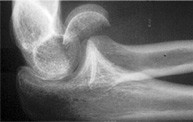

Axial view calcaneal fracture

Calcaneal Fracture CT